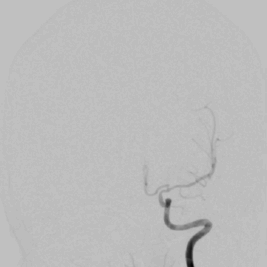

发病一周后完善了脑血管造影检查 。

正位

侧位

左侧大脑中动脉前向血流较同侧大脑前动脉缓慢。

3D:左侧颈内动脉C7段中度狭窄,左侧大脑中动脉M1段重度狭窄。